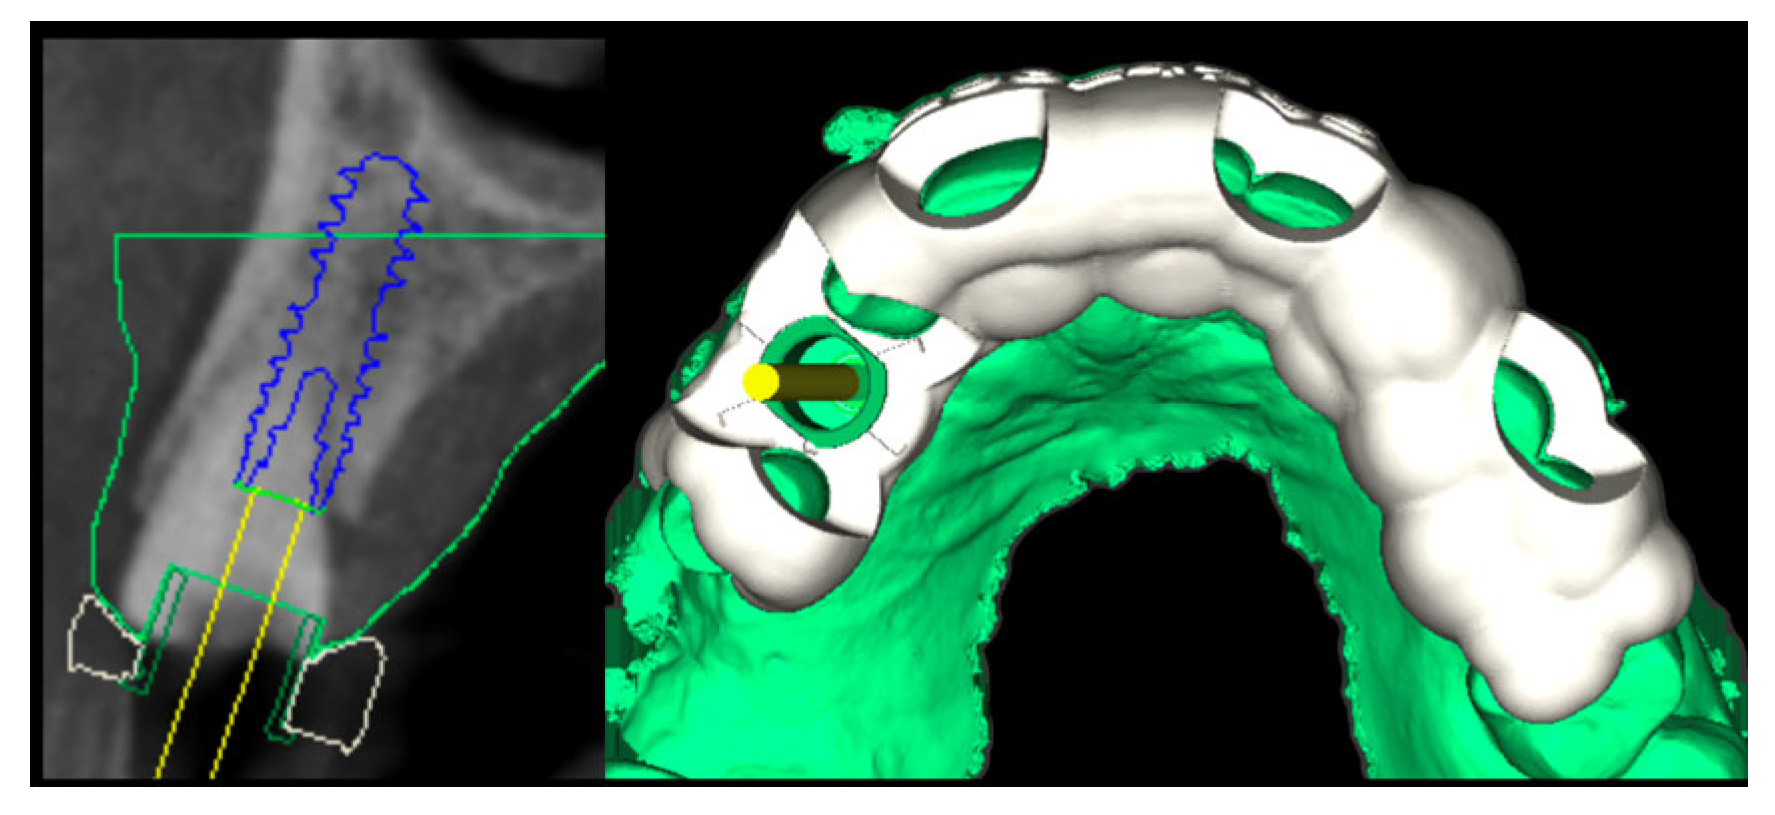

2.2. Surgery

2.3. Laboratory Procedure